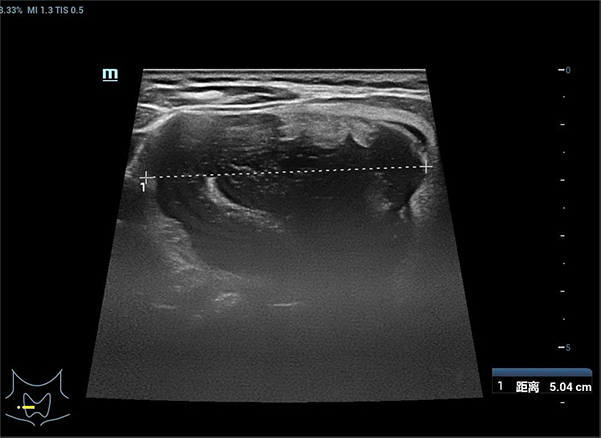

术前检查,甲状腺右叶囊实性结节直径5.04cm